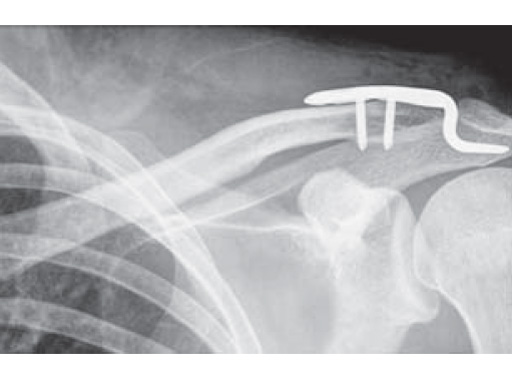

Fig.

Postoperative x-rays